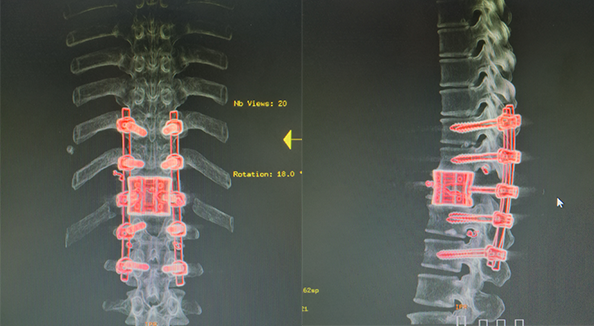

上两张病人的CT图先

术后3天病患已经可以下床进行简单的活动,真的是很成功的一次手术,在发一张病人于3个月后回医院复查的图来结束这个帖子的内容。

术后3天病患已经可以下床进行简单的活动,真的是很成功的一次手术,在发一张病人于3个月后回医院复查的图来结束这个帖子的内容。

上两张病人的CT图先

术后3天病患已经可以下床进行简单的活动,真的是很成功的一次手术,在发一张病人于3个月后回医院复查的图来结束这个帖子的内容。

术后3天病患已经可以下床进行简单的活动,真的是很成功的一次手术,在发一张病人于3个月后回医院复查的图来结束这个帖子的内容。